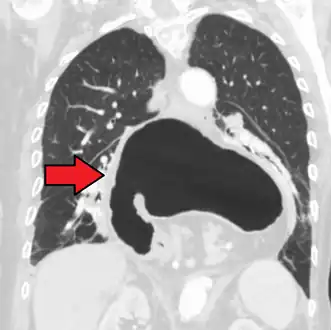

A large hiatal hernia on chest X-ray marked by open arrows in contrast to the heart borders marked by closed arrows

This hiatal hernia is mainly identified by an air-fluid level (labeled with arrows).